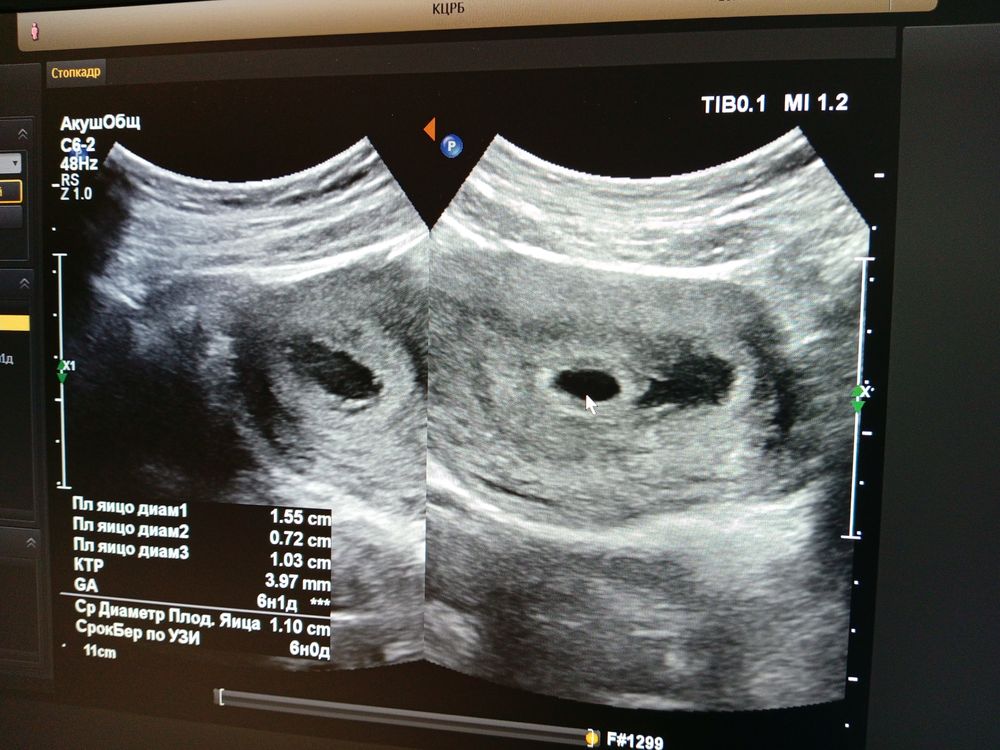

После утреннего туалета, на бумаге были выделения коричневого розовые, поехала в приёмный покой, там сделали узи

Есть угроза прерывания беременности, дали направления на госпитализацию в соседний город, еду ложиться 😢😭 хоть бы все обошлось 🙏🙏🙏

Назначили Дюфастон два раза в день по одной таблетке